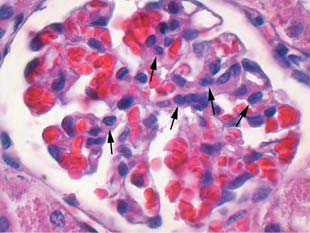

Базальные мембраны капилляров клубочков были утолщены, просвет капилляров сужен. Капсула клубочков почки выглядела утолщённой. Присутствовали синехии между париетальным листком капсулы и капиллярными петлями. Подоциты были увеличены в размерах, набухшие, c увеличенными ядрами, количество подоцитов при экспериментальном СД уменьшалось в 2,1 раза (рис. 4 и 5). В контрольной группе среднее число подоцитов в клубочке составило 4,9±0,4, а в группе сравнения — 10,2±0,2 (p=0,00002).

Рис. 4. В клубочках почек интактных животных подоциты небольшого размера и располагаются под эндотелием капилляров (отмечены стрелками). Окраска гематоксилином и эозином. Увеличение ×1600

Рис. 5. В клубочках почек экспериментальных животных на фоне склеротических изменений количество подоцитов уменьшено, они большого размера с крупными ядрами (отмечены стрелками). Окраска по Ван-Гизону. Увеличение ×1600